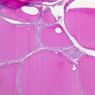

The thyroid gland (slide B-51, lead hematoxylin [10x, 20x, 40x, 40x]; B-52, H&E [10x-labeled, 20x, 40x-labeled, 40x]; B-53, PAS [2.5x, 10x, 20x, 40x]) consists of many closely packed, roughly spherical structures known as follicles, which are enclosed in a thick connective tissue capsule. Connective tissue septa extend from the capsule into the substance of the gland, carrying numerous blood vessels. Follicular cells are arranged as shells of simple cuboidal epithelium surrounding a gelatinous mass known as colloid. Look for a ring of epithelial cells around the homogeneous, pink-staining colloid. The cytoplasm of the follicular cells (principal cells) is faintly basophilic. The follicular cells secrete thyroglobulin, a glycoprotein, which is stored extracellularly in the colloid. In response to TSH, the follicular cells endocytose the colloid and hydrolyze it to form thyroxine. You can see where colloid has been resorbed because this process leaves small holes in the colloid adjacent to the follicular cells. These holes are known as resorption lacunae (B-52 [10x, 20x, 40xlabeled]). Very active follicles may exhibit a columnar epithelium and increased numbers of resorption lacunae. Between follicles, the stroma of the thyroid gland consists of a thin layer of connective tissue and a rich capillary network. Parafollicular cells (light cells or C cells) are located in the connective tissue between follicles or adjacent to follicular cells within follicles. When they lie within the follicular wall, the parafollicular cells do not reach the lumen. Parafollicular cells are slightly larger than the follicular cells and, in H & E preparations, have a more lightly stained cytoplasm (B-52, H&E [10x, 20x, 40x-labeled] [10x-labeled, 20x, 40x-labeled] [10x, 20x, 40x] [10x, 20x, 40x]; B-53, PAS [10x, 20x, 40x]). Parafollicular cells are readily identifiable in slide B-51 (stained with lead hematoxylin), where they appear as purplish-black structures in which the nuclei are difficult to discern (B-51 [10x, 20x, 40x-labeled]). These cells secrete calcitonin, which lowers serum calcium levels by inhibiting bone resorption and accelerating osteoid calcification.